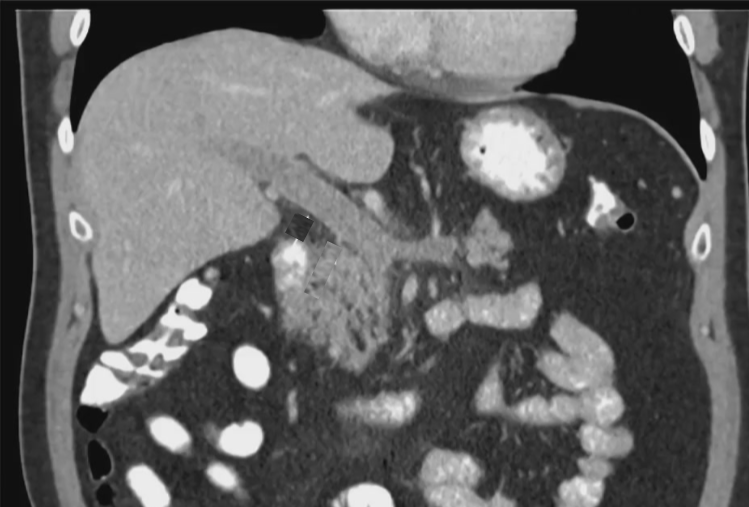

46 岁男性,伴有轻微腹痛和发热症状 诊断出门静脉(PV)和肠系膜上静脉(SMV)存在广泛的、严重的血栓形成。 病史:30 年前因摩托车事故接受脾脏切除手术

PVT(门静脉血栓)可能会导致门静脉高压以及侧支循环的形成以及肠道缺血。 抗凝治疗是常规疗法。然而,仅有 39%(6个月内)的患者能够实现门静脉的完全再通。 在血管内治疗技术方面的经验尚显不足,但这类技术确实提供了颇具前景的治疗方案【Pissier 2010】。 TIPS 与血栓切除术及 CDT 结合使用是治疗急性门静脉血栓形成的一种替代疗法,尤其适用于血栓范围广泛的病例。 有必要开展对比不同治疗方法的前瞻性研究,以明确这些方法的益处。 门静脉血栓形成:让“不可能”的经颈静脉肝内门体分流术成为可能……经脾静脉、肠系膜上静脉和肠系膜下静脉 |